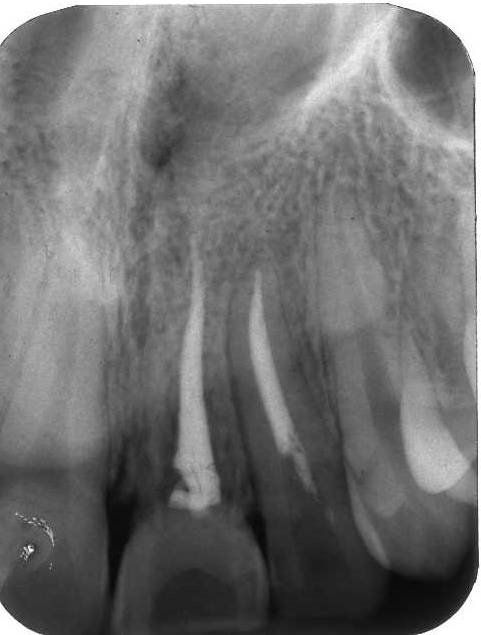

Radiograficamente è visibile il trattamento endodontico dell’incisivo laterale sinistro coinvolto anch’esso nel trauma. Sono visibili inoltre i dispositivi ortodontici necessari pe la sua estrusione al fine di recuperare l’ampiezza biologica, ovvero al fine di mantenere tre millimetri di tessuto dentale sano oltre il margine gengivale

Immagini radiografiche successive è possibile seguire negli anni l’evoluzione del dente reimpiantato. Nel corso degli la radice dell’incisivo centrale è andata in contro ad un progressivo riassorbimento per un atteso fenomeno di anchilosi.

L’anchilosi è un processo biologico infiammatorio che si verifica una volta che le fibre del legamento parodontale sono andate in necrosi e la superficie del cemento che ricompre la radice viene in contatto diretto con l’osso alveolare. In questa circostanza si attiva nei macrofagi una differenziazione in senso osteoclastico e dentino clastico che in pochi anni, talvolta in pochi mesi, porta al completo riassorbimento della radice e quindi alla sua scomparsa